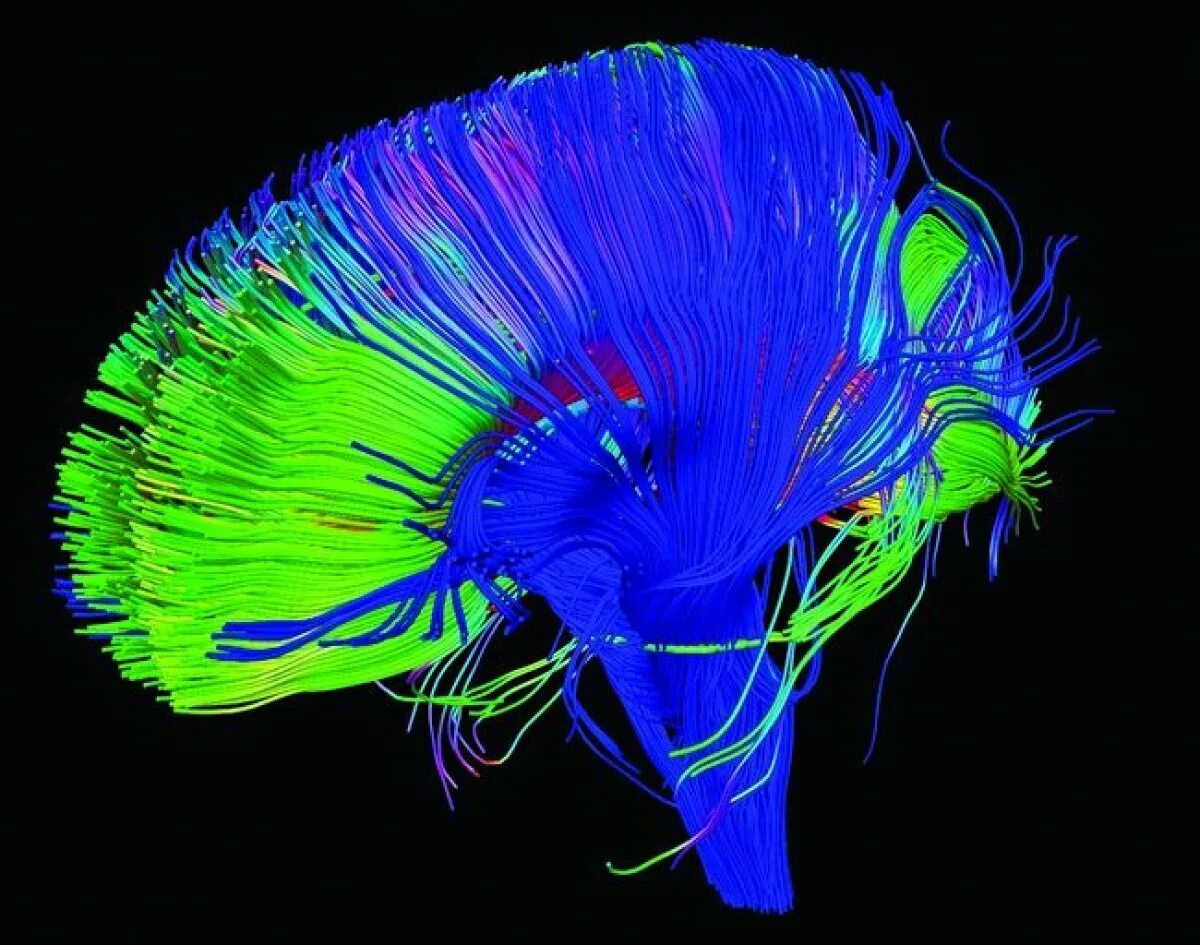

Diffusion tensor